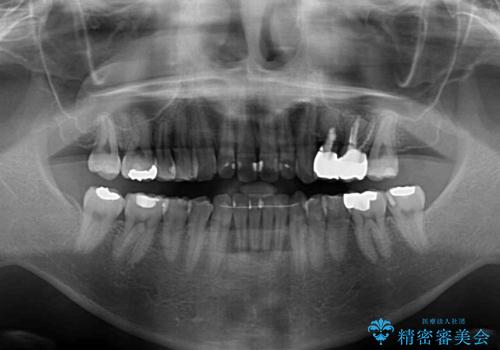

ボロボロとなっていた歯は抜歯が必要な状態でしたが、舌側転位している歯を移動させることで抜歯スペースを埋めることができるため、矯正治療により歯列を整えることとしました。

舌側転位の改善にインビザラインを用いるのはやや難易度が高くなりますが、前歯部のデコボコは軽度であったため、インビザラインによる矯正治療を行うこととしました。

矯正治療後には抜歯が必要な歯に隣接してむし歯となっていた歯をオールセラミッククラウンにて補綴治療を行うこととしました。

矯正治療開始時に、インビザライン矯正の加速装置を購入されましたが、インビザライン自体をあまりしっかりと使用できず、4年間の治療期間となりました。